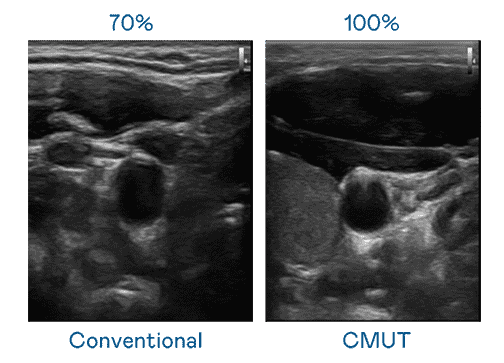

CMUT 技术是一种用电容式微机电元件来产生超音波讯号的技术。。。。与传统 PZT 压电式技术相比,,,,CMUT 频宽增加 30%,,,,更宽频的超音波讯号让影像解析度大幅提升,,,,是实现高影像品质医疗超音波扫描、、、、促进精准医疗发展的关键技术。。

超音波影像的解析度高低,,,,首先取决于探头能发出的讯号频宽。。。YAXIN111 CMUT 可提供高清晰的超音波讯号,,,,提供高频宽、、高灵敏度、、、、影像纹理细节更高的超音波影像,,,,协助医护人员缩短影像判读时间及利用精准的医疗影像进行诊断。。。